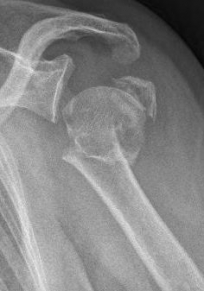

Picture: The subcapital humeral fracture shown here in the axis is not broken and only slightly bruised, so that a conservative therapy is possible. The left image shows the follow-up after 3 weeks. The patient has already started physiotherapy. The x-ray shows an increase bone healing.